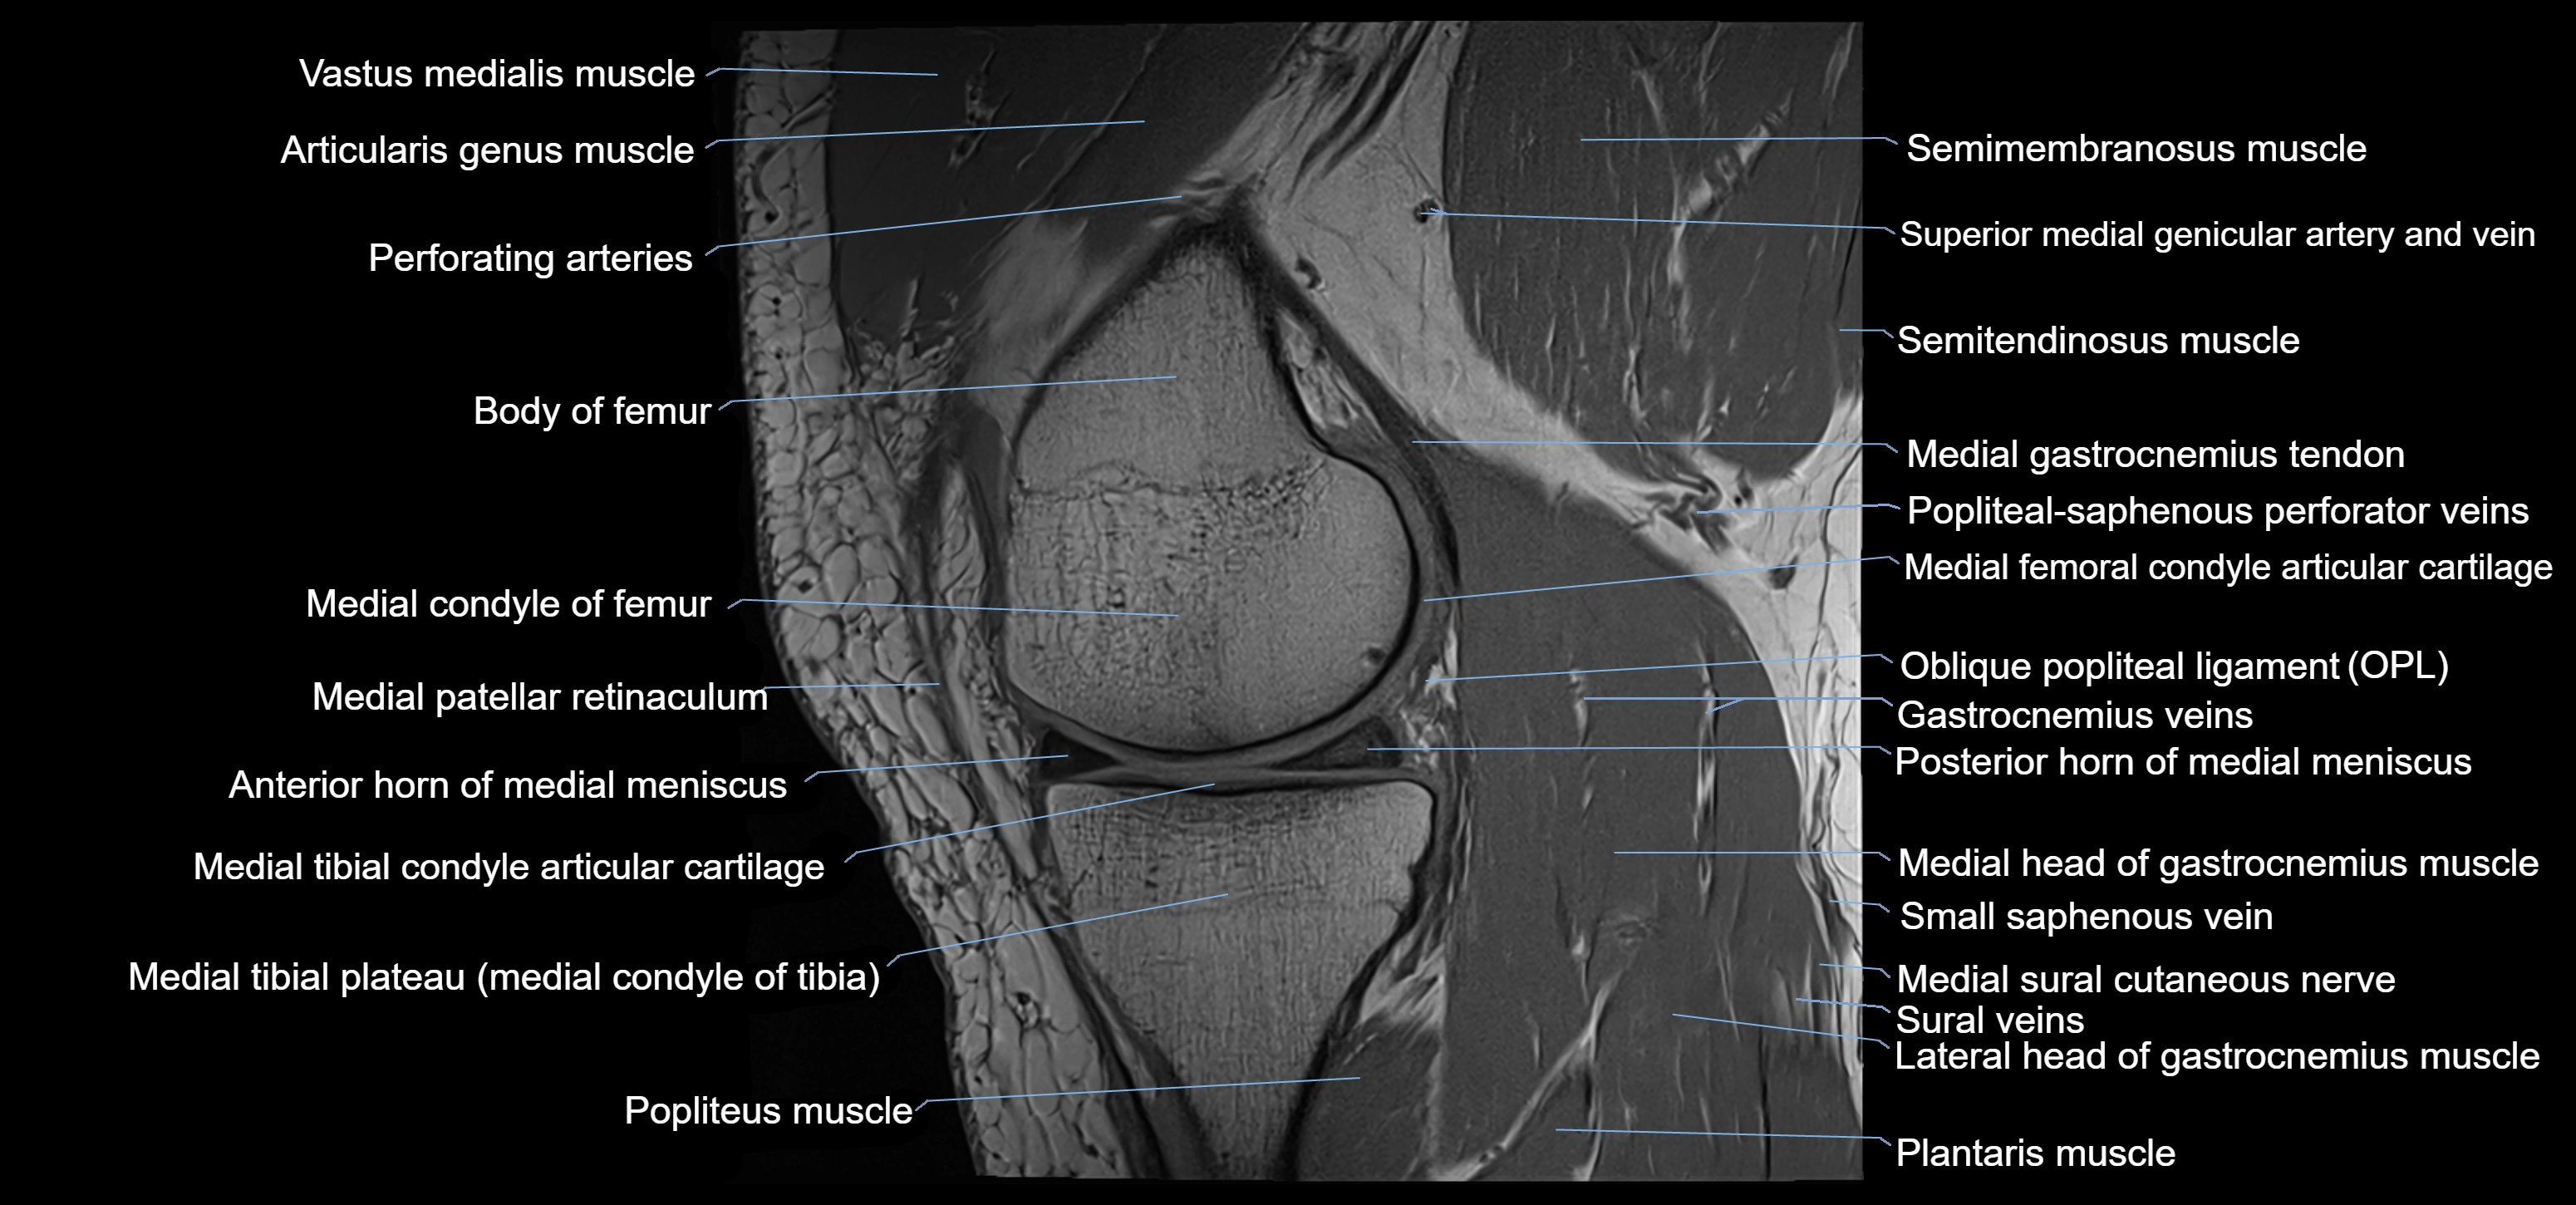

- Anterior horn of medial meniscus

- Body of femur

- Body of medial meniscus

- Distal semimembranosus tendon

- Medial condyle of femur

- Medial condyle of tibia

- Medial gastrocnemius tendon

- Medial head of gastrocnemius muscle

- Medial meniscus

- Medial patellar retinaculum

- Medial tibial plateau

- Oblique popliteal ligament

- Popliteus muscle

- Posterior horn of medial meniscus

- Semimembranosus muscle

- Semitendinosus muscle

- Small saphenous vein

- Superior medial genicular artery

- Superior medial genicular vein

- Vastus medialis muscle